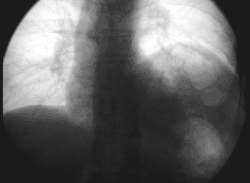

Left phrenic nerve palsy (right image side) in fluoroscopy: forced inspiration with the closed mouth leads to paradox elevation of the paralytic left diaphragm while the healthy right side moves down.